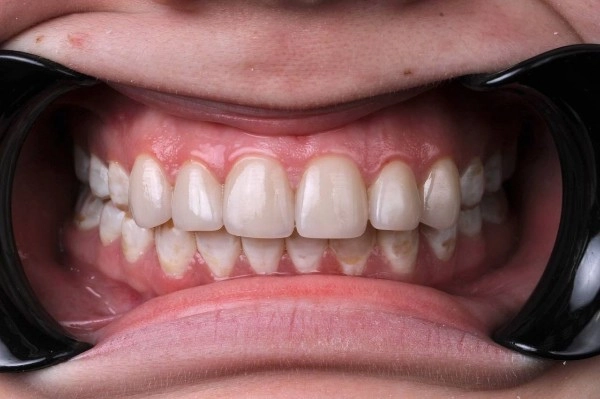

Как вылечить флюороз: ⠀

На начальном этапе проводится отбеливание, а затем назначается курс реминерализации. Возможно назначение медикаментов.⠀

При поражениях средней и тяжелой степени восстановить эмаль естественным образом уже невозможно. Вернуть зубам эстетичный вид можно при помощи композитных материалов, керамических виниров или коронок.⠀

На фото работа врача стоматолога - ортопеда Сергеевой Анастасии Сергеевной.